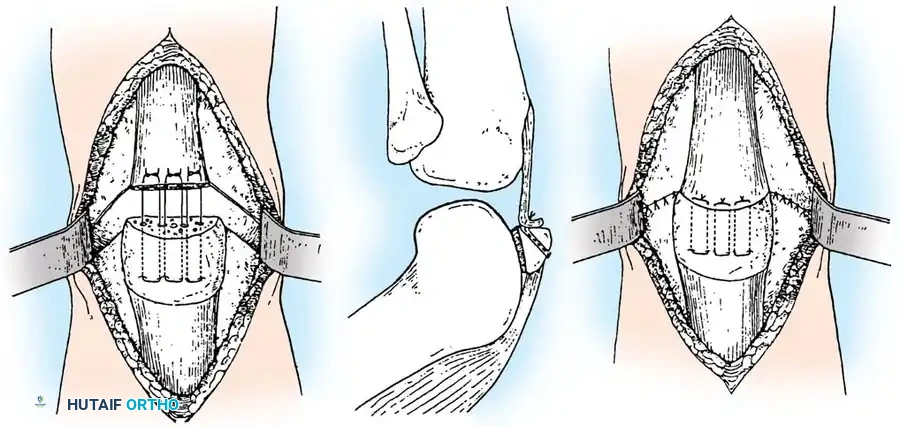

Tension Band Wiring Principles

Wiring techniques are most frequently utilized for transverse fractures. The fundamental biomechanical principle of the tension band is the conversion of tensile forces acting on the anterior cortex of the patella (generated by the quadriceps) into compressive forces at the articular surface during knee flexion.

Weber et al. experimentally compared the rigidity of various constructs, including circumferential wiring, standard tension band wiring, Magnusson wiring, and modified tension band wiring (utilizing two anteriorly placed wires combined with two transfixing longitudinal Kirschner wires). They concluded that the most secure fixation was achieved with the modified tension band wiring technique. Weber emphasized anchoring the fixation wire directly into the bone rather than threading it solely through the soft tissues if early motion is to be initiated.

Surgical Warning: When tensioning the wire, ensure symmetric tightening. Use heavy pliers or a wire tensioner to pull the wire taut before twisting, ensuring the twist does not simply coil upon itself but actively compresses the fracture site.

Cannulated Screw Fixation with Tension Band

Recent biomechanical advancements have popularized the use of cannulated screws combined with a tension band wire. Carpenter et al. demonstrated that transverse fractures fixed with a tension band wire passed through parallel cannulated screws failed at the highest load compared to K-wires or screws alone.

Berg described the fixation of displaced transverse fractures using a figure-of-eight wire passed through parallel cannulated compression screws. Advantages of this construct include:

* A low-profile construct that minimizes hardware irritation (a common complication of K-wires backing out).

* Enhanced interfragmentary compression provided by the lag screws.

* Superior biomechanical stability allowing for aggressive early restricted motion.

* Utility as a salvage method following the failure of traditional tension band wiring.

For transverse fractures with large, robust fragments, a tension band modified with cannulated screws is currently the preferred technique. If peripheral comminution is present, a supplemental circumferential cerclage wire can be added.